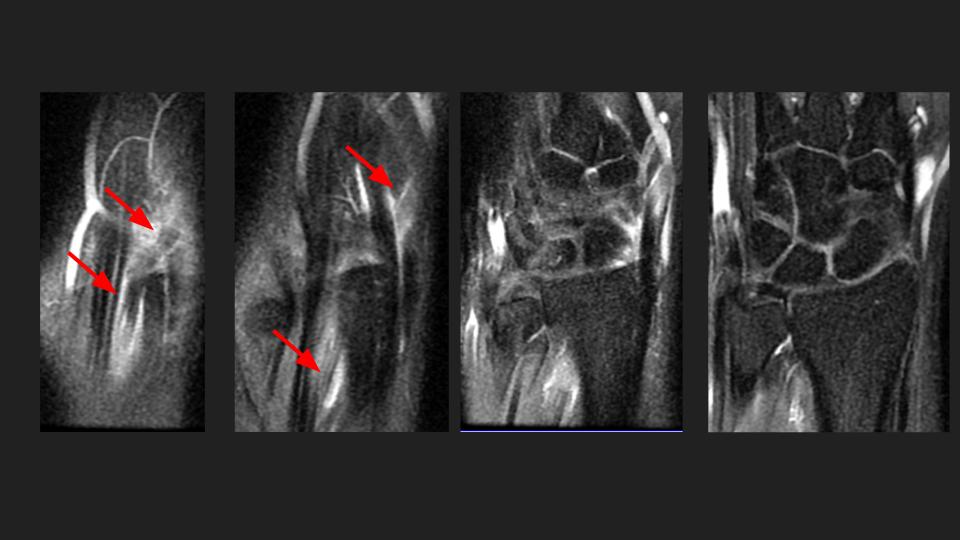

35M 5 months pain, referred to evaluate the scapholunate ligament

Red arrows point to the EPL which appears partially torn proximal to the level of Listers tubercle. On MRI (I wish this were US, I hear you) the distal remnant at the site of intersection with the 1st extensor compartment looks quite attenuated, but I see something passing over ECRL/ECRB with fluid signal between. Is this a complication of neglected proximal intersection syndrome? I have never seen it progress to EPL tear, but apparently there are Italian radiologists (see attached abstract) who have. Reference article.

extensor pollicis longus tendon ( RID2378 )